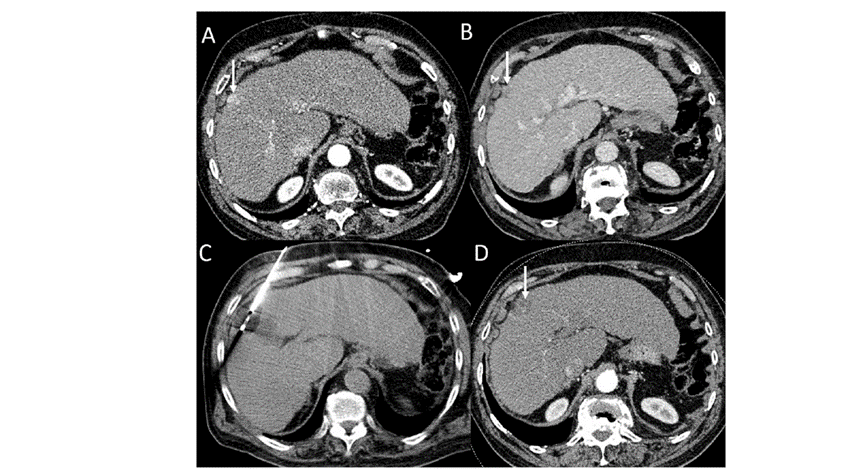

(A)動脈期CT圖像顯示有一個(gè)包膜下結(jié)節(jié)(箭頭)。(B)門靜脈期CT圖像顯示病灶區(qū)(箭頭)。(C) 在手術(shù)過程中的CT顯示一個(gè)冷凍探針位于病灶內(nèi)。(D)消融后,術(shù)后1個(gè)月影像CT顯示完全消融。患者在手術(shù)及住院期間無并發(fā)癥及重大并發(fā)癥發(fā)生。隨訪時(shí)間中位數(shù)為7個(gè)月(范圍:3-12個(gè)月),隨訪期間患者無局部腫瘤進(jìn)展或死亡。

技術(shù)成功率為100%,本研究中77.8%(7/9)的患者達(dá)到了完全消融,輔助局部治療后,所有患者均完全消融。

膽囊附近轉(zhuǎn)移灶(來自子宮頸癌)的冷凍消融術(shù)(A)門靜脈期 CT 圖像顯示膽囊附近有病變(箭頭)。(C) 手術(shù)過程中CT 顯示冷凍探針位于病灶內(nèi)。(D)消融手術(shù)后 1 個(gè)月CT 顯示完全消融。

本研究中患者隨訪期間無局部腫瘤進(jìn)展,無死亡病例,沒有發(fā)現(xiàn)與手術(shù)相關(guān)的并發(fā)癥。證實(shí)冷凍消融是一種有效的治療方式,在技術(shù)上是可行和安全的。由于肝包膜下病變位置特殊,射頻消融有出血及腫瘤種植的風(fēng)險(xiǎn),可能會對鄰近器官造成損傷,并且增加局部腫瘤進(jìn)展的風(fēng)險(xiǎn)。近年來,冷凍消融術(shù)的應(yīng)用逐漸廣泛,有研究顯示冷凍消融治療具有明顯優(yōu)勢,可治療特殊部位的肝腫瘤。本研究的目的是評價(jià)冷凍消融治療肝包膜下腫瘤的安全性和有效性。回顧性納入2016年7月1日至2018年9月1日期間冷凍消融的57例患者。包括42例男性和15例女性,平均年齡為62.4歲(范圍:48-82歲)。每個(gè)患者有1個(gè)或2個(gè)平均腫瘤尺寸為2.4cm的病變(范圍:0.6-4.0cm)。所有患者均患有慢性肝病或肝硬化,并伴有乙型肝炎(n=52)、丙型肝炎(n=3)和其他肝炎(n=2)。根據(jù)腫瘤位置,在膈肌或肝臟下附近有18個(gè)病變(26.5%),胃或腸附近有9個(gè)病變(13.2%),腹壁附近有33個(gè)病變(48.5%),腎臟附近有8個(gè)病變(11.8%)。